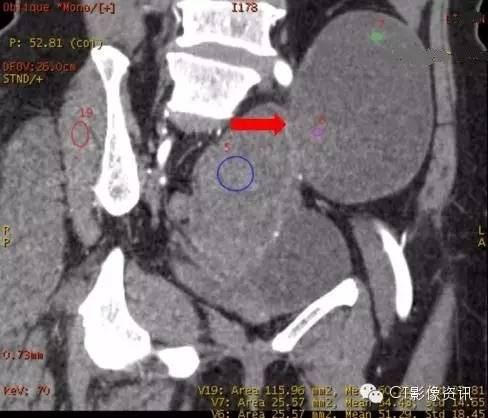

3、能谱曲线分析

小结 能谱曲线可以进行同源性分析,即通过能谱曲线的相似与否来提示病变是否有相似性。但需要注意的是使用能谱曲线时要用动态的思维来考量。例如:该病例的动脉期与延迟期的能谱曲线的变化既说明病灶的起源相似性,又说明病灶供血的特征性,为临床提供了更多的病变信息,指导临床诊疗方案的制定。